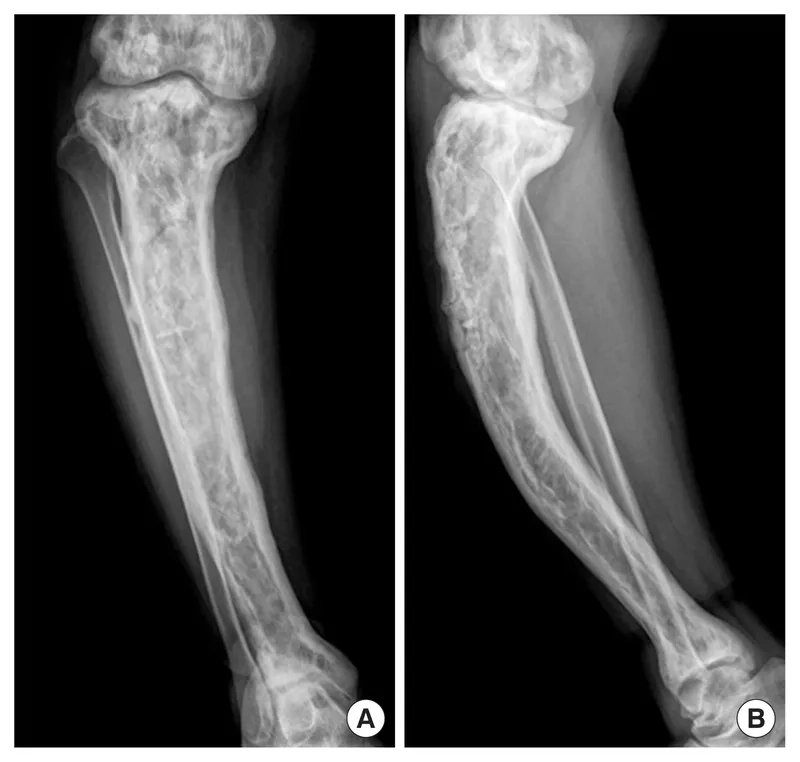

An X-ray showing bone changes from Paget's disease